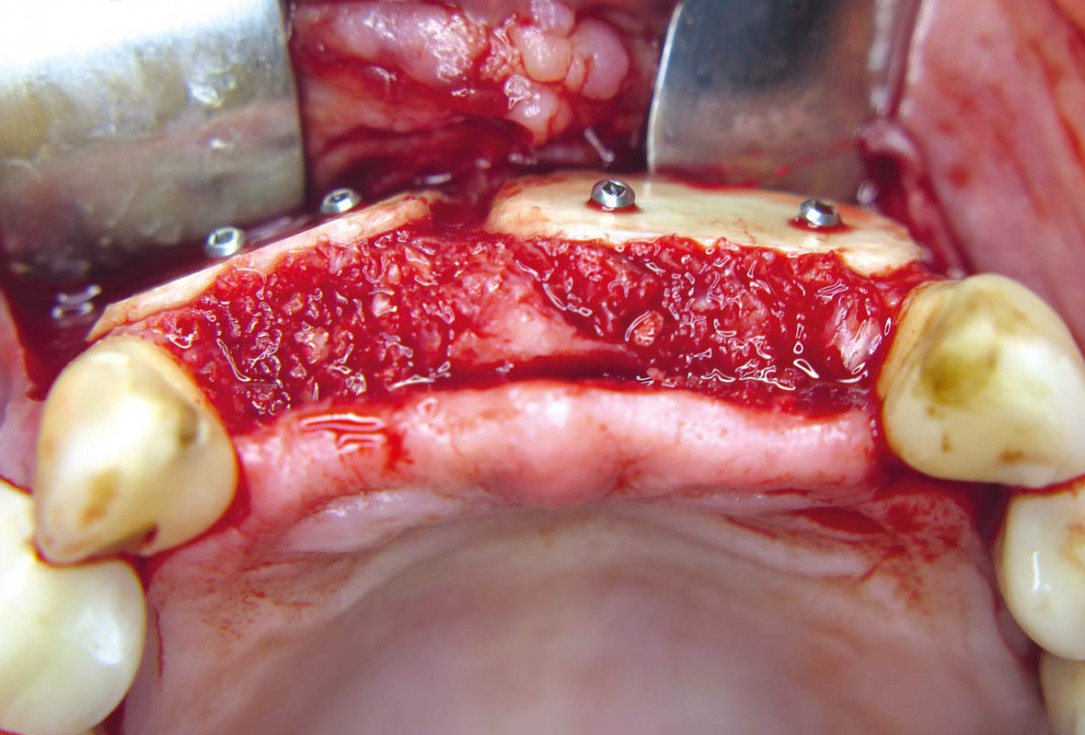

05 / 22 - Fixation of two allogenic cortical plates at the buccal wall

Three-dimensional augmentation with maxgraft® cortico - M.Sc. E. Kapogianni

06 / 22 - Crestal fixation of two allogenic cortical plates for container creation and contouring with cancellous allogenic chips